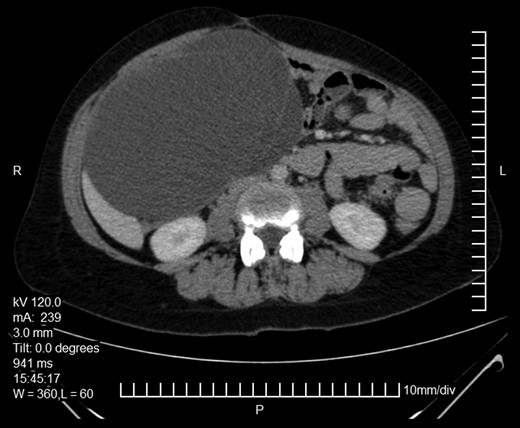

Here we report on a 32-year-old patient who presented at the Emergency Department complaining of acute abdominal pain accompanied by vomiting and diarrhea that had started three hours before. The patient was a para 2 and the latter delivery had occurred nine months before. She had been breastfeeding until 20 days before her ED visit and her menses had not yet resumed. Her medical history was unsignificant and she reported a laparoscopic ovarian cystectomy five years before, of which the histology report was not retrieved. She also had an ultrasound six months before, which described a pelvic multilocular cystic lesion of 11.4 × 8,6 × 12.3 centimeters, which remained untreated. The patient underwent an IV contrast—enhanced abdominal CT which demonstrated sizeable multilocular bilateral ovarian cystic lesions, of 18 cm and 15 cm in dimensions (in the right and left ovary respectively). (Figs 1 and 2). Her tumor markers were as follows (normal values are in parentheses): CA 15.3 = 20.53 U/ml (<25 U/ml), AFP = 1.08 ng/ml (<7 ng/ml), CEA = 0.63 ng/ml (<3.8 ng/ml), CA 125 = 110.40 U/ml (<35 U/ml), CA 19.9 = 50.06 (<34 U/ml), CA 72.4 = 6.74 (<6.9 U/ml). After the completion of preoperative investigations, the patient underwent and exploratory laparotomy. Frozen section revealed bilateral serous borderline tumors, therefore the patient underwent a total abdominal hysterectomy/bilateral salpingoophorectomy and epiplectomy. During surgical procedure astonishing remarks was the necrotized torsion of ovarian masses mimicking infiltrated ovarian neoplasm. (Figs 3–5). The final histology report confirmed the diagnosis of bilateral serous borderline tumors/atypical serous proliferative tumors, staged as pT1cNxMx or FIGO Ic. (Figs 6 and 7). Peritoneal fluid cytology showed mesothelial reactive lesions. The patient’s postoperative course was uneventful. The Multidisciplinary Team Meeting decided on adjuvant chemotherapy (four cycles of CarboTaxol; paclitaxel and carboplatin). Nine months after surgery, the patient remains alive and disease – free.

Abdominopelvic CT. Bilateral ovarian masses with characteristic diaphragms.